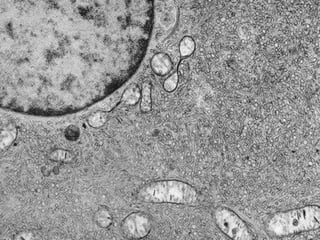

Este documento presenta imágenes microscópicas de diferentes tipos de tejidos y estructuras celulares teñidas con varios métodos histológicos. Incluye fotografías que muestran fibras de colágeno, elásticas y reticulares en diversos órganos, así como membranas basales y células especializadas de órganos como riñones, glándulas mamarias y próstata. El propósito es demostrar la aplicación de técnicas histológicas para visualizar componentes celulares y tej